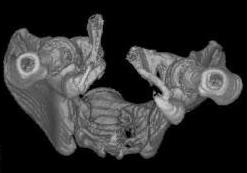

Уважаемые коллеги! Девушка 18л сросшиеся переломы лонных, седалищных костей с обеих сторон, перелом крестца справа,перелом костей голени справа (зио), 3 мес после травмы, АВФ снят с таза.

Патологической подвижности нет. Стоит самостоятельно, ходит с костылями, поскольку 3 месяца практически не ходила. Беспокоит выступание лонной кости в области лобка, хотя объективно грубого косметического дефекта нет. На кт разворот лонной кости в сагиттальную плоскость. Вопрос: стоит ли добиватьсяполной репозиции или же достаточно произвести остеотомию верхушки выступающего отломка?

Предварительный диагноз- посттравматическая вертикальная нестабильная деформация таза II степени, неправильно срастающийся перелом боковой

массы крестца справа, правой лонной и седалищной костей, застарелый разрыв лонного сочленения.

Для уточнения диагноза ниеобходимы обзорные рентгенограммы таза (прямая и inlet), Кт срезы на уровне переломов для определения степени сращения и решения вопроса о методе оперативного восстановления анатомии (делать ли остеотомию, низводить ли задние отделы), ни о какой "остеотомии выступающих отломков" тем более у девочки 18 лет речи быть не может.